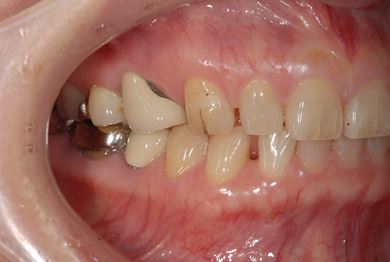

インプラントの症例写真 IMPLANT

インプラント治療

| 性別/年齢 | / 49歳 | ||||||||||||||||||||||||||||||||

| 主訴 | 乳歯がぐらついている。 | ||||||||||||||||||||||||||||||||

| 治療方針 | インプラント治療にて、機能的・審美的回復を行う。 | ||||||||||||||||||||||||||||||||

| 治療内容 | インプラント1本、メタルボンドセラミッククラウン1本 | ||||||||||||||||||||||||||||||||

| 総治療費 | 377,055円 | ||||||||||||||||||||||||||||||||

| 治療期間 | 4ヶ月 |